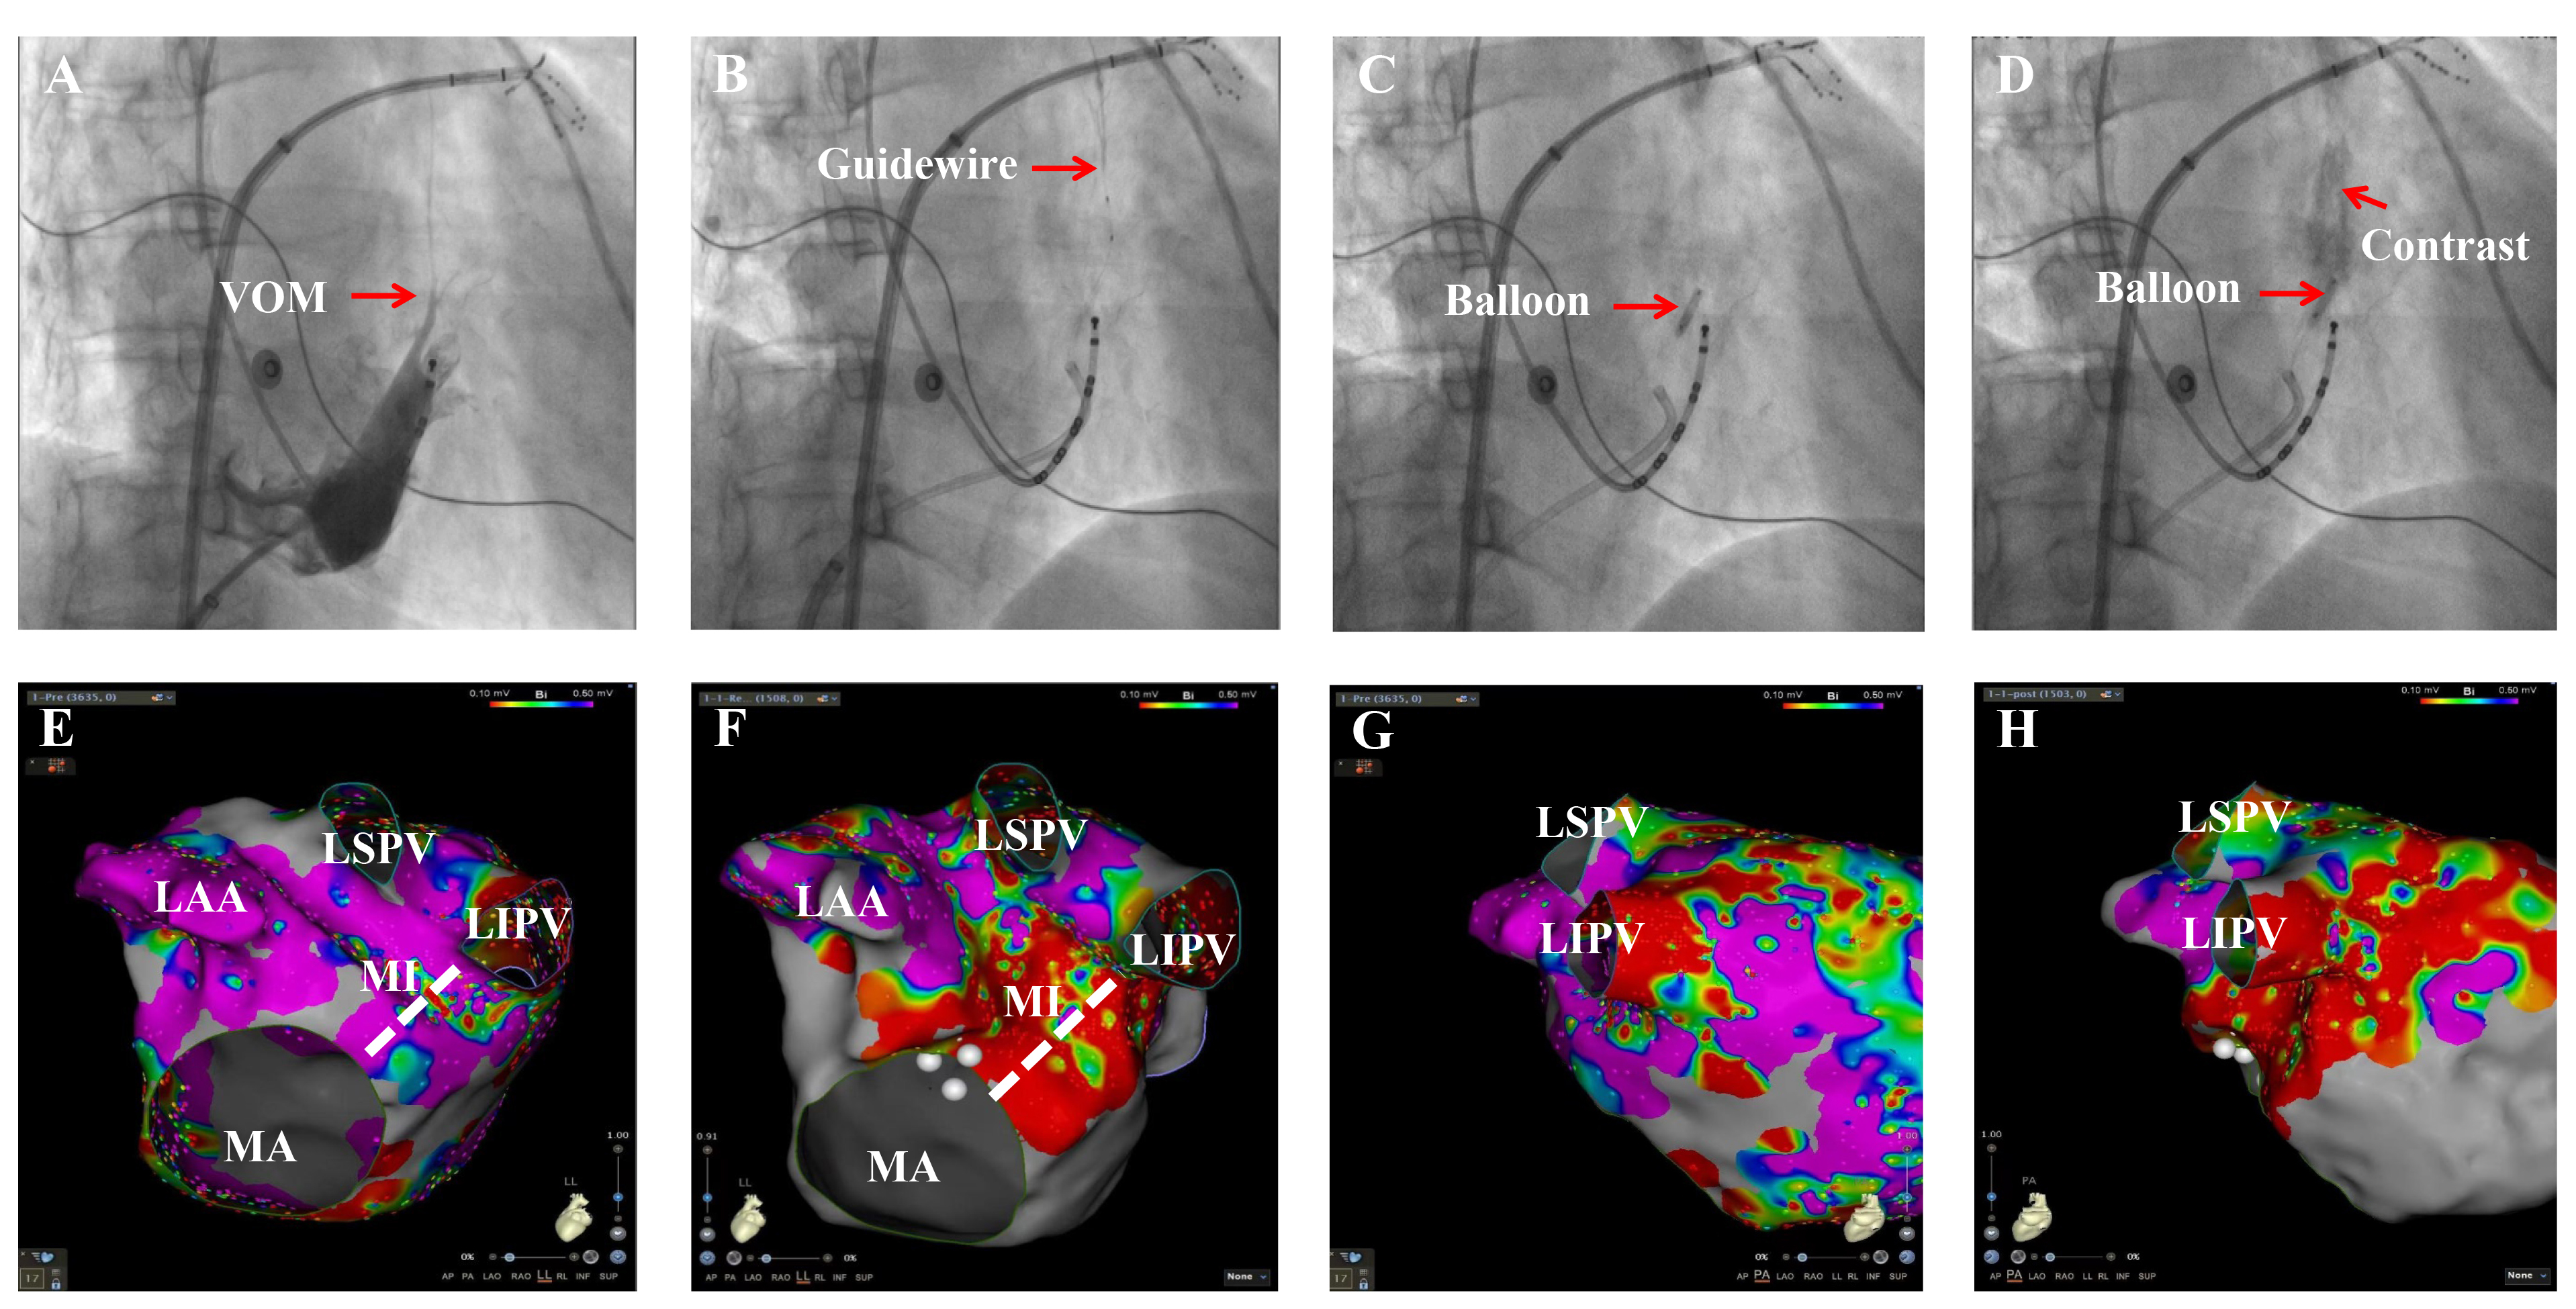

Fig. 1.The procedural steps of the vein of Marshall (VOM) ethanol infusion (VOM-EI). (A) Angiography of the VOM in 30° right anterior oblique (RAO) views. (B) Guidewire in the distal end of the VOM. (C) The proximal end of the VOM sealed by the dilational balloon. (D) Ethanol-infused tissue was stained. (E) Voltage mapping of the left pulmonary veins, left pulmonary vein-LAA ridge region, and the posterior before VOM-EI in left lateral (LL) views. (F) Voltage mapping showed low-voltage regions in the posterior MI and left pulmonary vein-LAA ridge region, after VOM-EI. (G) Voltage mapping of LIPV before VOM-EI in posteroanterior (PA) views. (H) Voltage mapping in LIPV showed low-voltage regions after VOM-EI. LAA, left atrial appendage; LSPV, left superior pulmonary vein; LIPV, left inferior pulmonary vein; MI, mitral isthmus; MA, mitral annular. The red arrow marks the VOM in Fig. 1A, the guidewire in Fig. 1B, the balloon in Fig. 1C, and the contrast agent and the balloon in Fig. 1D, respectively. The white dashed line marks the MI in Fig. 1E,F.

The VOM-EI procedure was routinely administered before the RFCA procedure in all

patients. Intravenous heparin administration maintained an activated clotting

time of 300–350 seconds. After transseptal punctures, three-dimensional

anatomical reconstruction and the high-density voltage mapping of the left atrium

(LA) were performed using a Pentaray Nav eco high-density mapping catheter

(Biosense Webster, Diamond Bar, CA, USA) under the guidance of the CARTO3

electroanatomical mapping system (Biosense Webster, Diamond Bar, CA, USA).

Baseline left atrial bipolar voltage mapping was performed in the AF rhythm in

all patients, and any low voltage was noted. In patients in the VOM +RFCA group,

voltage mapping was repeated after VOM-EI and limited to the ethanol-infused VOM

region. The color scale ranged from 0.1 to 0.5 mV. A voltage below 0.1 mV was

defined as scared myocardium, and a voltage above 0.5 mV was defined as normal

myocardium. The region where the bipolar voltage was